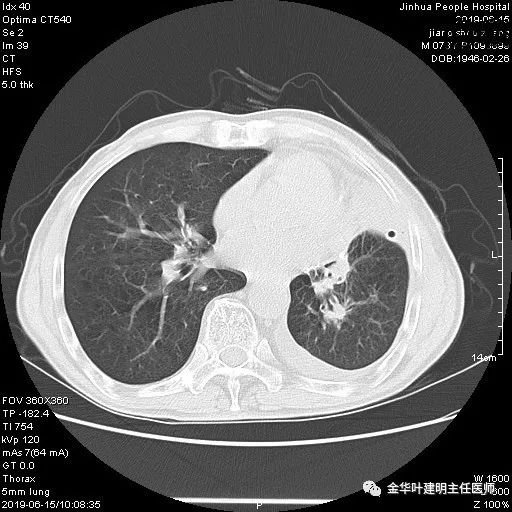

患者,男性,73岁,金华人。因“咳嗽咳痰伴胸闷2月,检查确诊左肺癌1周”入院。气管镜: 气管支气管内较多脓性分泌物,左肺上叶前段管腔新生物,局部活检、毛刷。气管镜病理:(左肺活检)鳞癌。阅胸部CT见左上叶开口处新生物,考虑需左上叶袖式切除及淋巴结清扫。具体CT表现如下:

6.15上午:24小时胸管引流出血性液250ml;复查胸部CT示: